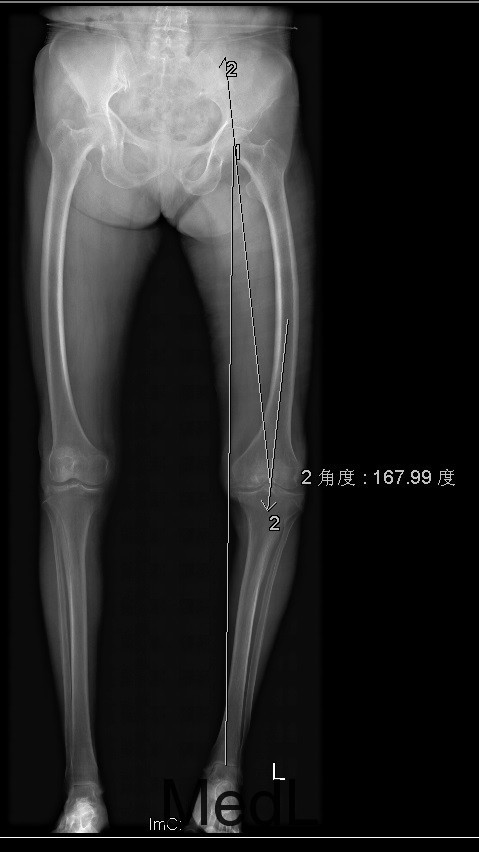

查体:跛行步态,左侧股内侧肌萎缩,左膝内侧关节间隙压痛,左膝髌股关节间隙压痛。左膝伸-45°,屈90°,左膝屈伸活动时髌骨下摩擦感 (+)。 辅助检查:左髌股关节内侧间室变窄,关节边缘骨赘增生,软骨下骨硬化

诊断:1、左膝骨关节炎伴屈曲畸形 2、左髌骨骨折骨愈合 治疗:积极行术前准备后于全麻下行左侧全膝关节置换术+软组织松解术,术后常规治疗。

患者术后功能良好,症状缓解,生活治疗提高 1、股骨外翻截骨如何在X线片上定角度?